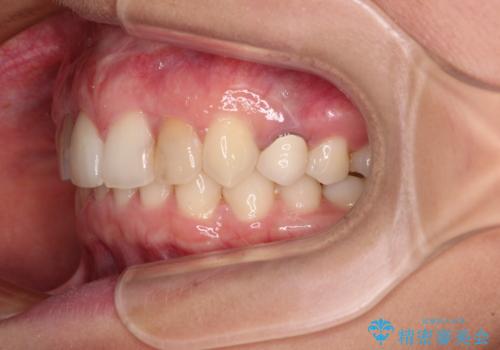

- 前歯の歯並びと神経を取って変色してしまった前歯を気にして来院された患者様です。

上下前歯の歯列不正はインビザラインにより整え、その後に、前歯2本をオールセラミッククラウンにて補綴治療することとしました。

下顎前歯が1本欠損しており、下顎歯列の大きさが本来よりも小さいため、上顎歯列とのバランスが悪く、深い咬み合わせになっていました。

上顎にIPRを多用して歯列の大きさを小さくするよう試みましたが、理想的な咬み合わせまでには改善させることはできませんでした。